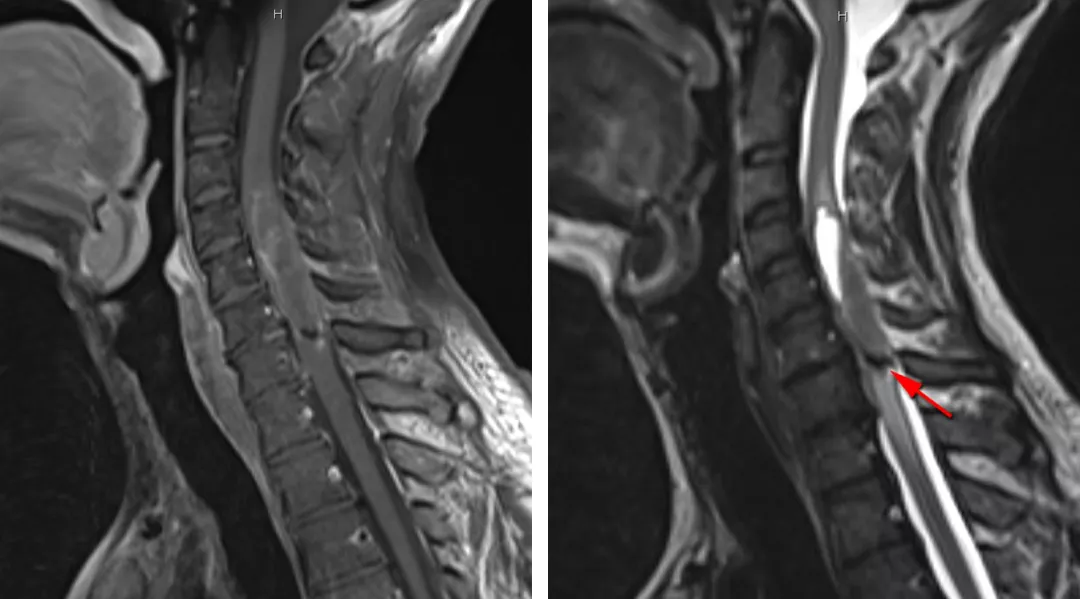

图3:图中所示为一名VHL患者胸髓血管母细胞瘤伴多发髓内病变。注意巨大肿瘤位于脊髓偏心位置且伴一大型囊肿。

图4:图中所示为伴囊变的胸髓毛细胞型星形细胞瘤,此病理类型肿瘤主要位于脊髓背侧,呈偏心性生长。不同于更高级别的胶质瘤,毛细胞型星形细胞瘤多边界清楚,表现为压迫脊髓而非浸润性生长。